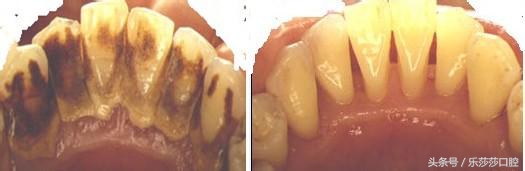

八:牙结石分度:牙结石「有多有少」,不同的「牙齿部位」其数量不一样,我们可以根据牙结石的多少「测量」自己刷牙的质量,为清洁口腔作参考。

九:洗牙前后:洗牙如同洗澡,医生通过专业工具将牙齿表面牙垢清除赶紧,恢复牙齿本色。另外,洗牙时将牙结石这种「假性保护」清洁掉,所以会觉得牙缝变大。